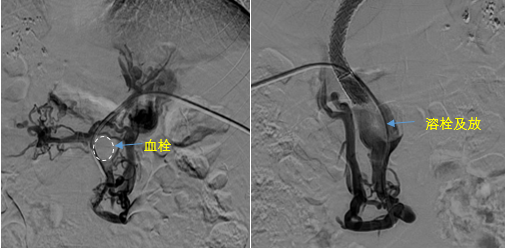

• 血栓攔路,如何破局——罕見巨大門靜脈血栓TIPS手術(shù)實錄

血栓攔路,如何破局——罕見巨大門靜脈血栓TIPS手術(shù)實錄

日前,西安國際醫(yī)學中心醫(yī)院消化病醫(yī)院為一位罕見巨大門靜脈血栓患者行TIPS手術(shù)。將患者體內(nèi)的“定時炸彈”拆除。9月份的一天,李女士晚飯后發(fā)覺惡心,嘔吐出鮮紅色的血塊,隨即又出現(xiàn)了黑便。在醫(yī)院檢查發(fā)現(xiàn)是食管胃底靜脈曲張破裂出血。……